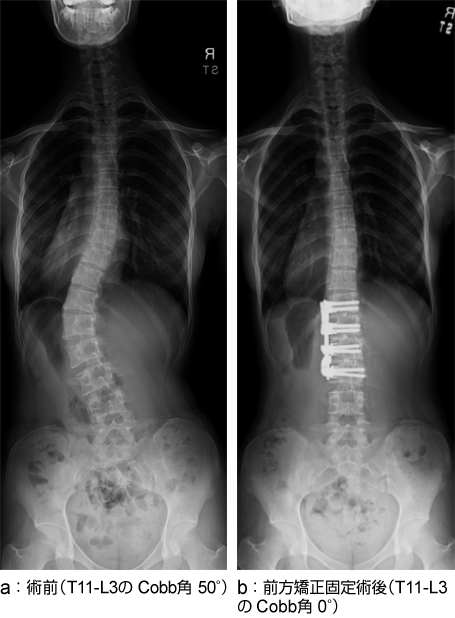

特発性側弯症(腰椎カーブ)の立位全脊柱X線正面像

T11-L3にCobb角50°の腰椎カーブを認めた(a)。前方矯正固定術により、Cobb角は0°に矯正された(b)。後方固定に比較し多くは固定範囲を少なくすることができる(可動椎間を多く残すことができる)。